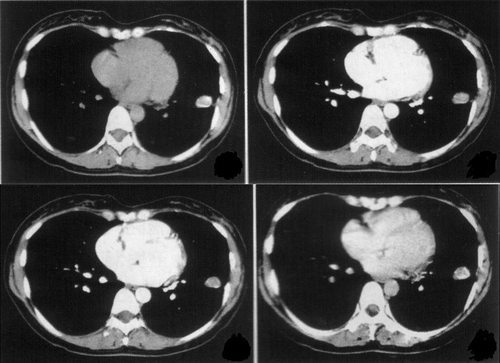

最后,对于疑似有肺部疾病的患者,医生一般会建议进行胸片或胸部的CT平扫检查。如果发现有该病的症状,医生会根据检查的结果来判断患者是否需要再次通过采用肺部加强CT造影剂进行扫描。